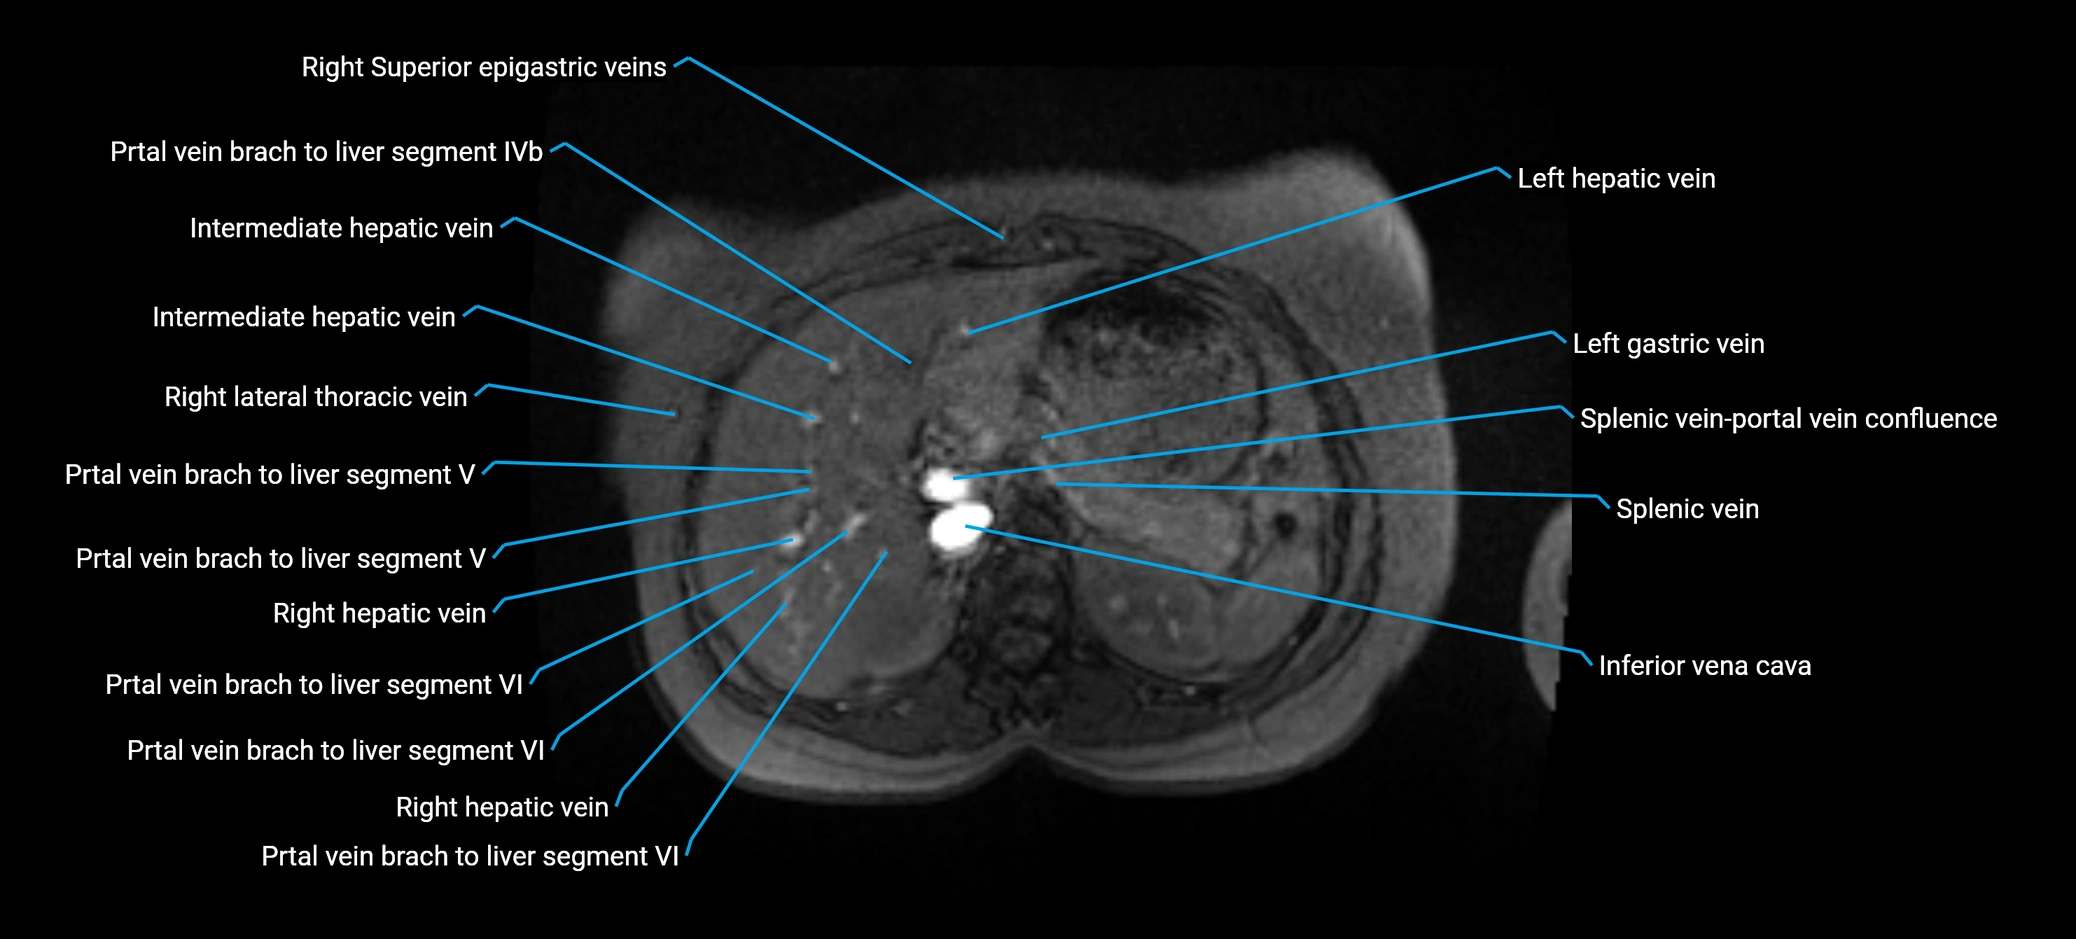

MRI image

image